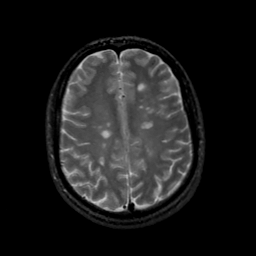

MR Study #18, July 21, 1991 -- Slice #35

[Home][Help][Clinical][Tour 1][Tour 2] Slice 35